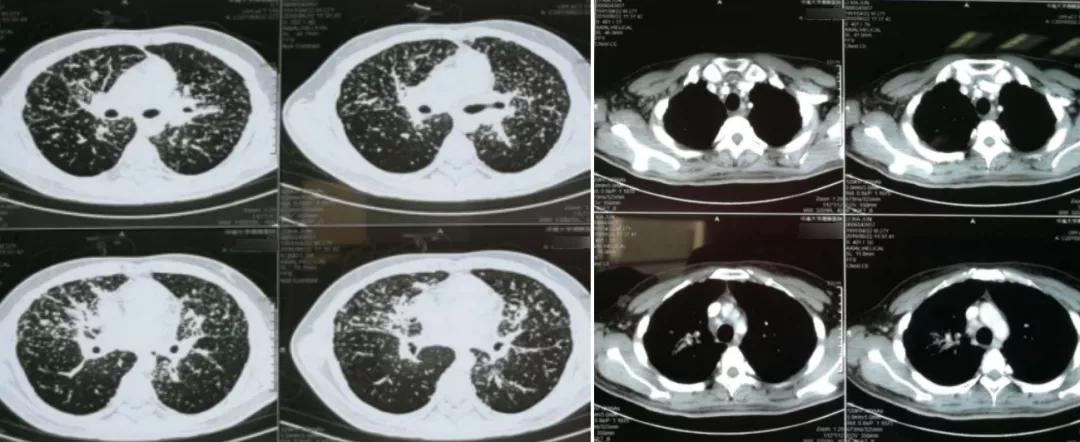

胸部CT(2017年3月)两上肺结节及斑片影,纵隔及双侧肺门淋巴结肿大(图1)。

肺部CT(2018年8月)双肺结节及斑片影较前明显增多,但纵隔和双肺门淋巴结较前缩小(图2)。

图1:肺部CT 2017年3月

图2:肺部CT 2018年8月